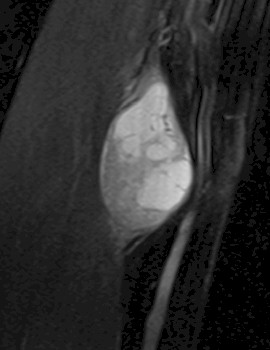

Como exploraciones complementarias se realizó una ecografía y una resonancia magnética (RM) que describió un tumor sólido en la continuidad del nervio mediano, de baja densidad y sin realce vascular (figuras 1a y 1b).

Figuras 1a y 1b: Imágenes de la resonancia magnética (RM) en las que observamos un corte en el plano parasagital y en el plano transversal de la tumoración a nivel del brazo.